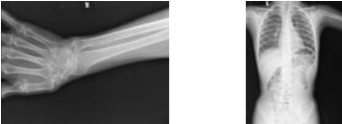

(2)X光机透视拍照(图345)。头颅CT片(图346)。

图344 这车圆木多少立方

图345 X光机透视拍照

图346 头颅CT片